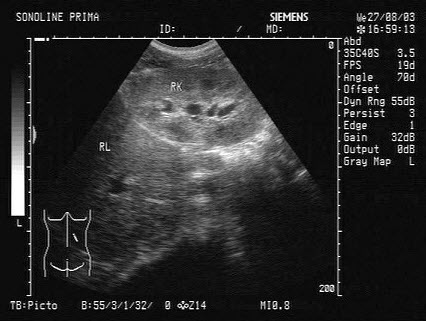

255、单项选择题

某患者行右心造影,心尖四腔心切面声像图所示,提示为()

A.室间隔缺损

B.动脉导管未闭

C.房间隔缺损

D.正常结构

E.二尖瓣狭窄